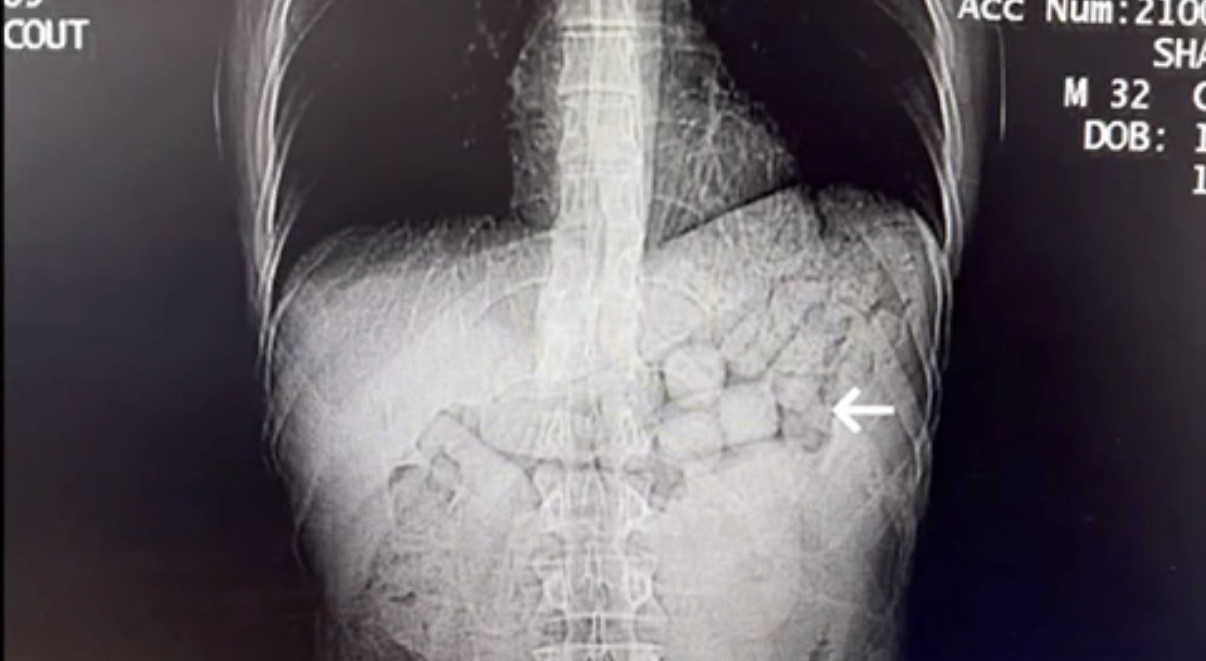

Bahse konu şahısların çekilen tomografi görüntülerinde, mide ve bağırsak bölümlerinde yabancı cisimlere rastlandı.

Yaklaşık 3 gün süren kontroller sonucunda şahıslardan; 91 kapsül halinde 807,15 gram Metamfetamin maddesi ele geçirildi ve şüpheliler gözaltına alındı.